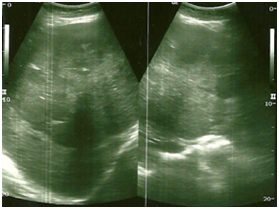

The CT scan with endovenous contrast demonstrated liver enlargement because of four nodular formations irregularly distributed and of various sizes, presenting the largest about 12,5x10 cm in the segments II, III, IV and VIII, expansive, hypodense with well-delineated contours, with heterogeneous impregnation after the infusion of the contrast, with a tendency to the homogenization in the late phase (Figure 2). It also demonstrates dilation of the intrahepatic biliary duct in the left hepatic lobe, probably of obstructive aspect due to the hepatic injury of greater dimension, not observing dilation of the extra-hepatic biliary duct and not characterizing the gallbladder.

Figure 2 The CT scan with endovenous contrast (arterial phase) demonstrated liver enlargement because of four nodular formations irregularly distributed and of various sizes, affecting the segments II, III, IV, VII, expansive, hypodense with well delineated contours, with heterogeneous impregnation after the infusion of the contrast.